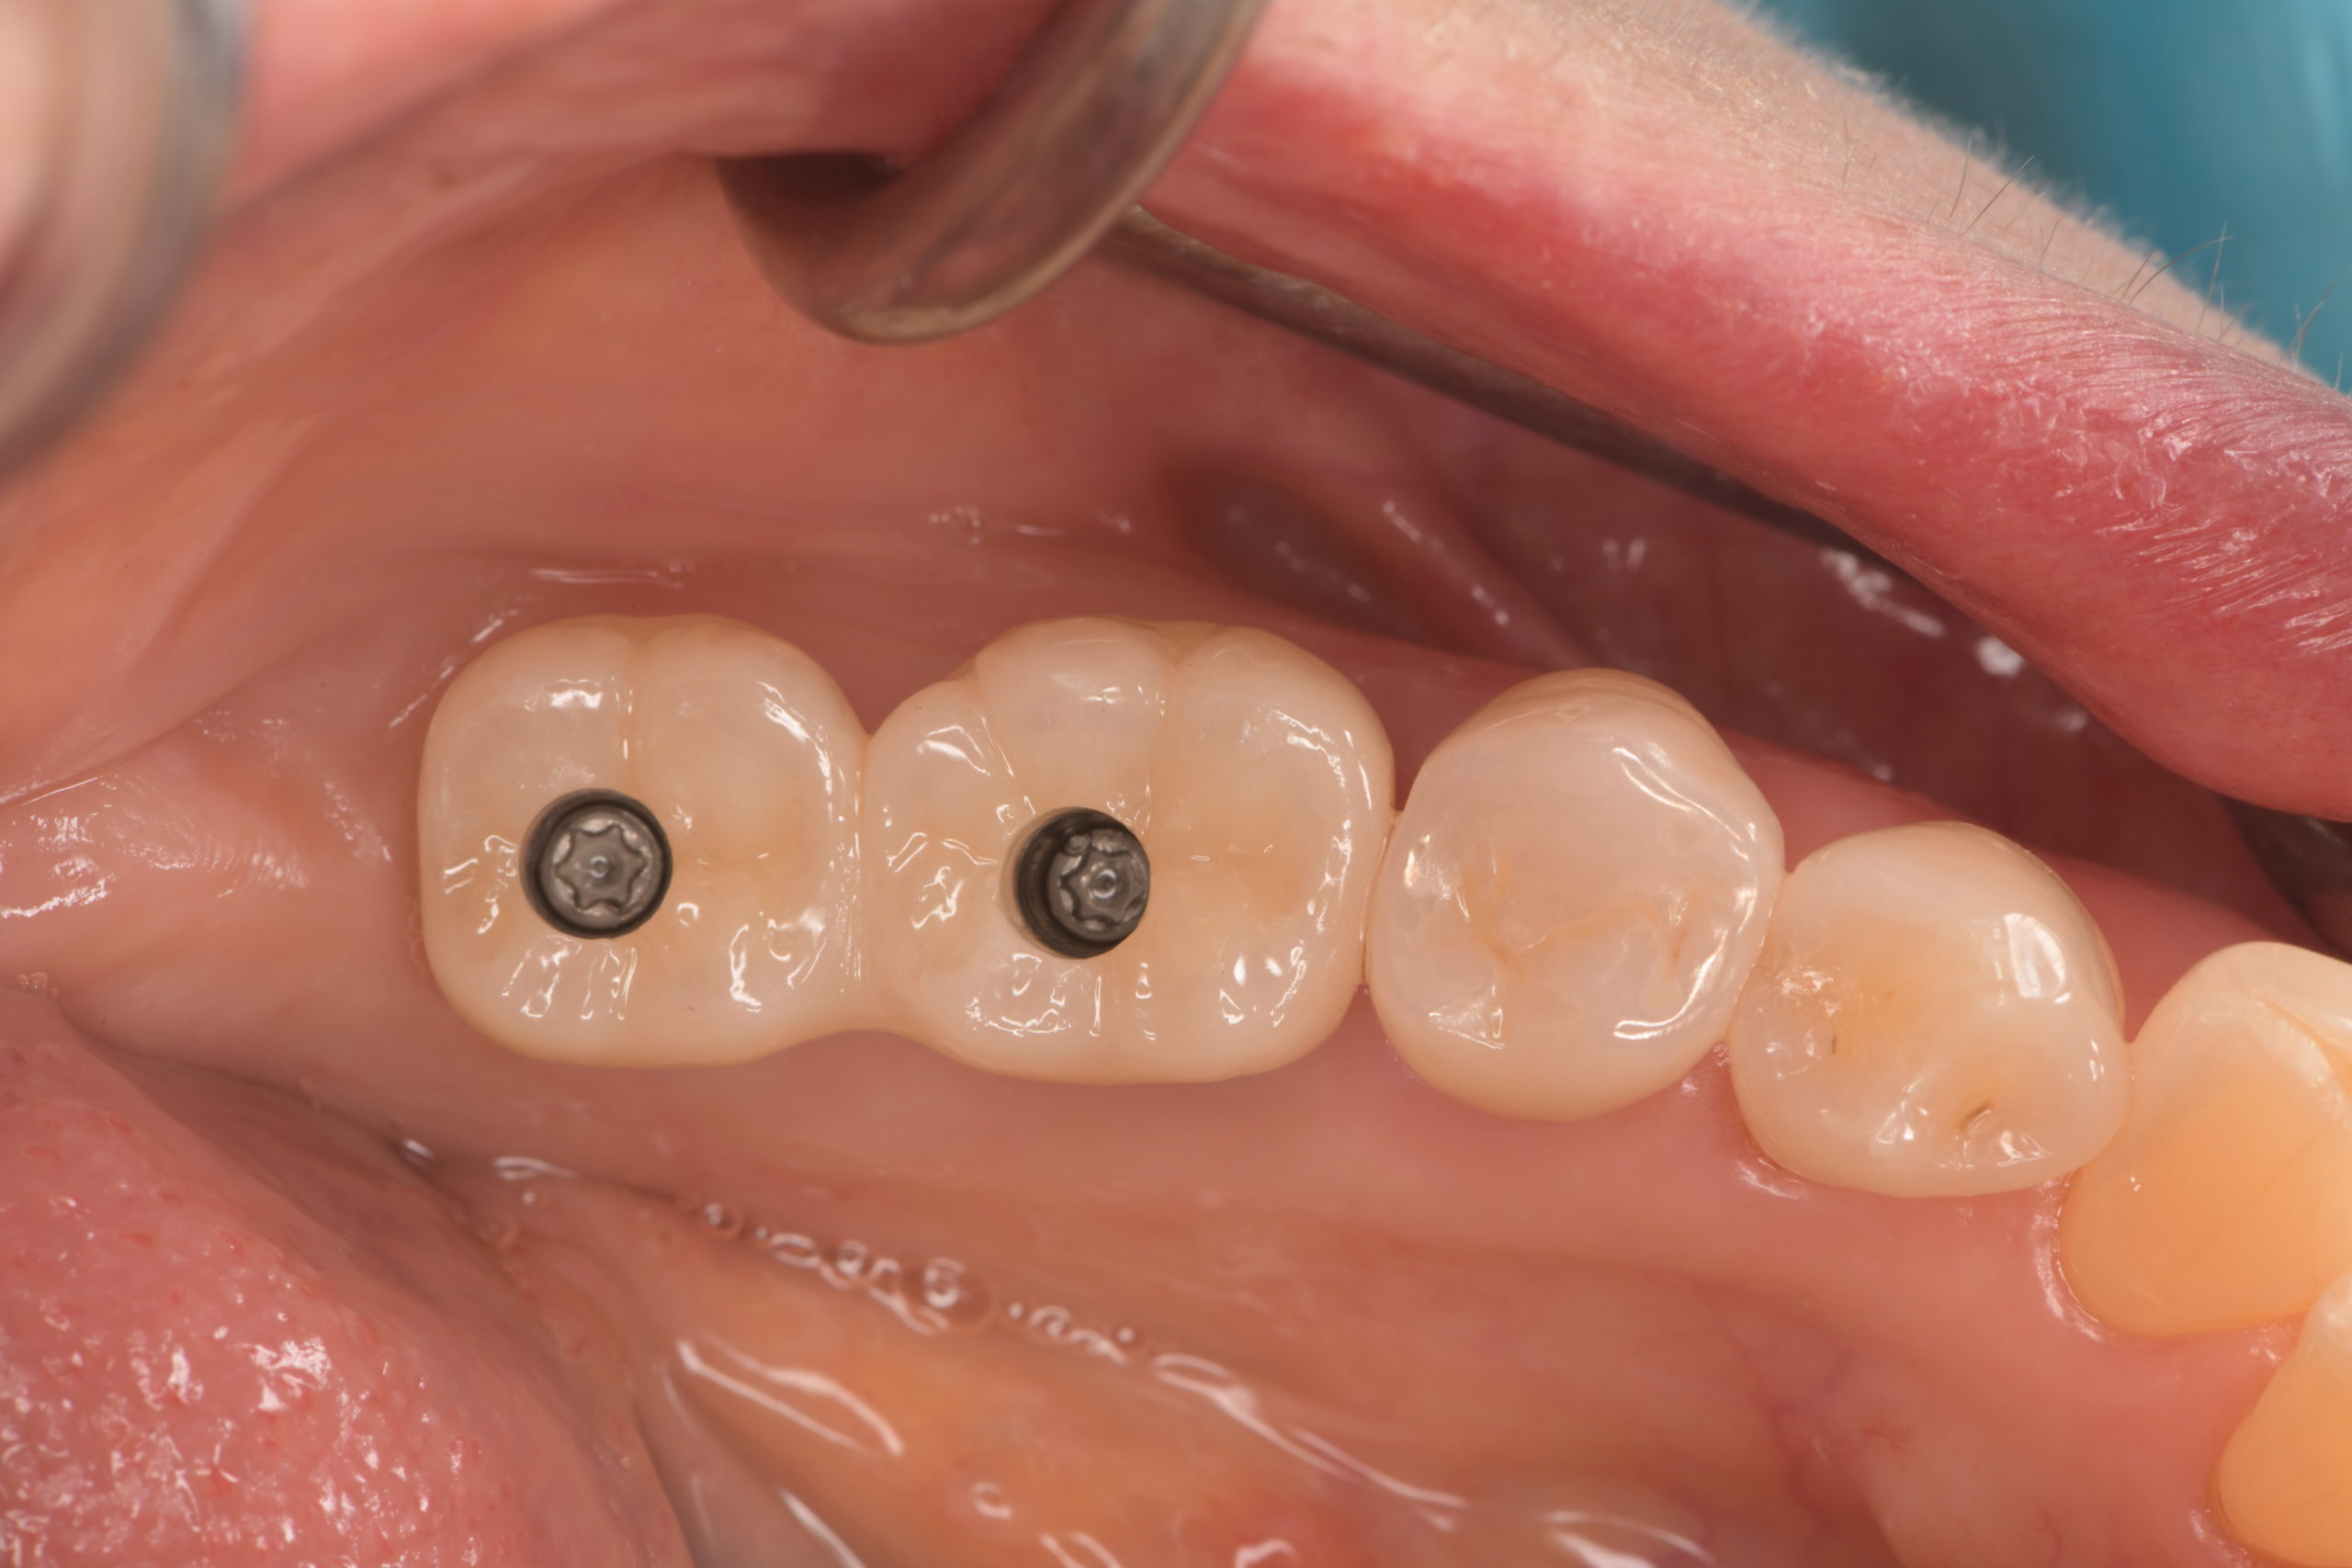

上顎臼歯部インプラント治療前

上顎臼歯部インプラント上部構造装着前

上顎臼歯部インプラント治療完了